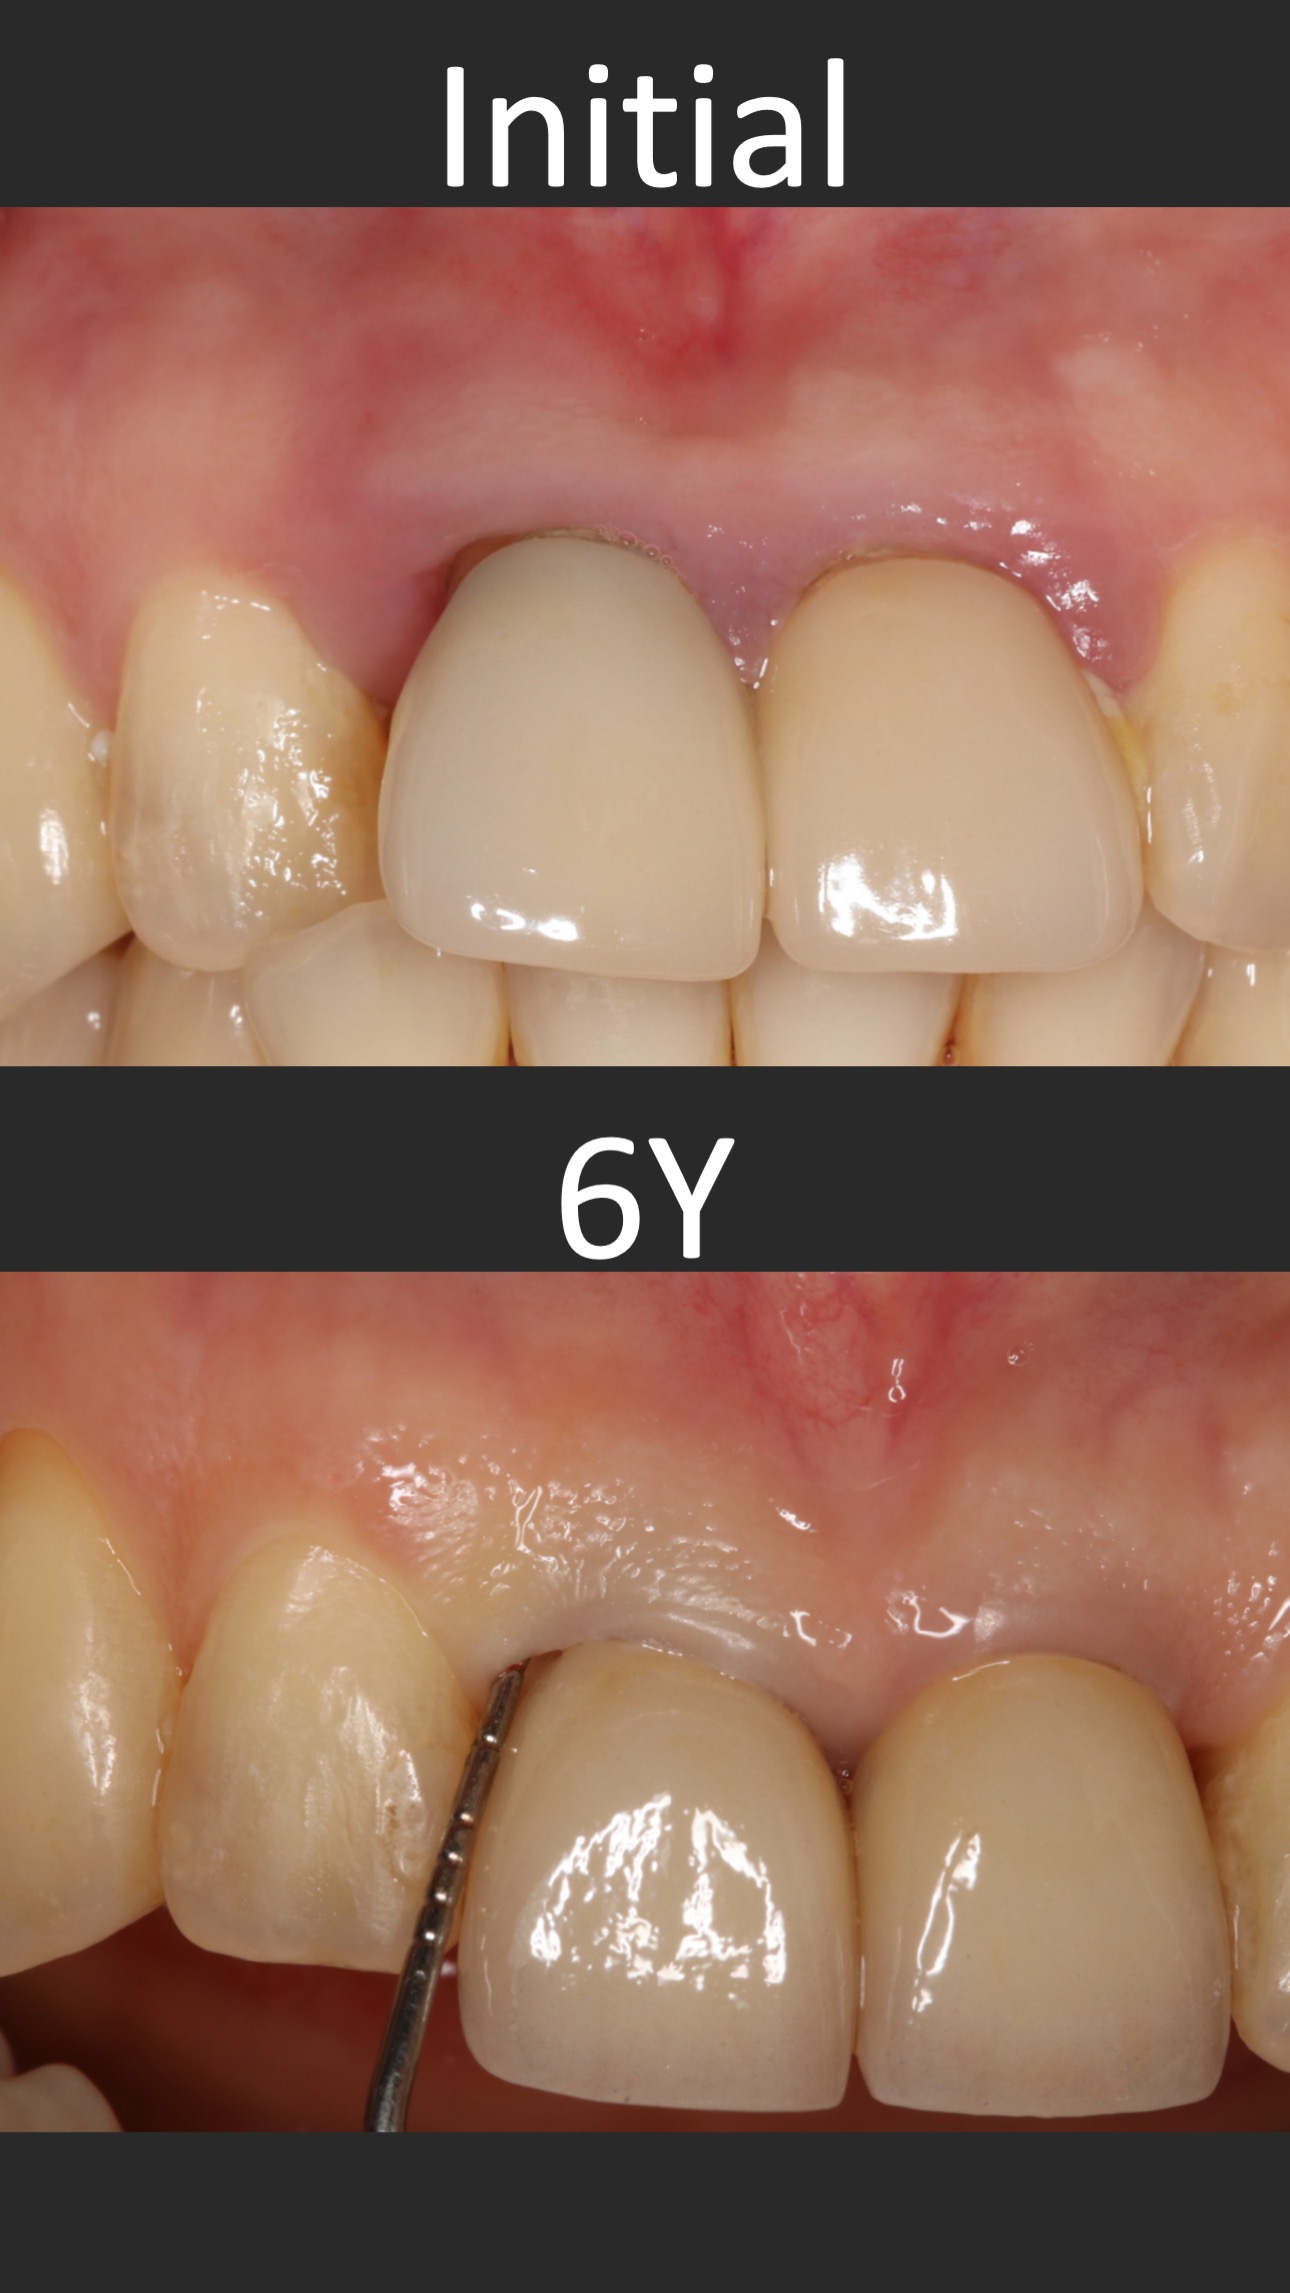

這個案例,最早沒把握能救回來,但是做完非手術治療,發現恢復非常好。

於是大膽地請矯正與假牙專科醫師一起幫忙完成。其實病人本身也同意,若途中狀況不好,還是得拔除。我知道這種案例,其實對其他專科來說,可能是有壓力的,不容易處理,也是難症。

好佳在,兩位神隊友都完成了,非常感謝合作專科的信任,還有,病患六年來維持得非常好,目前囊袋正常、零出血、零發炎。

回頭看,一開始就拔掉牙齒,改走其他路線,或許也可以,每位醫師選擇的或許不一樣,並沒有標準答案。

但是,能幫病患留下自己的牙齒,真的是很開心的一件事~~